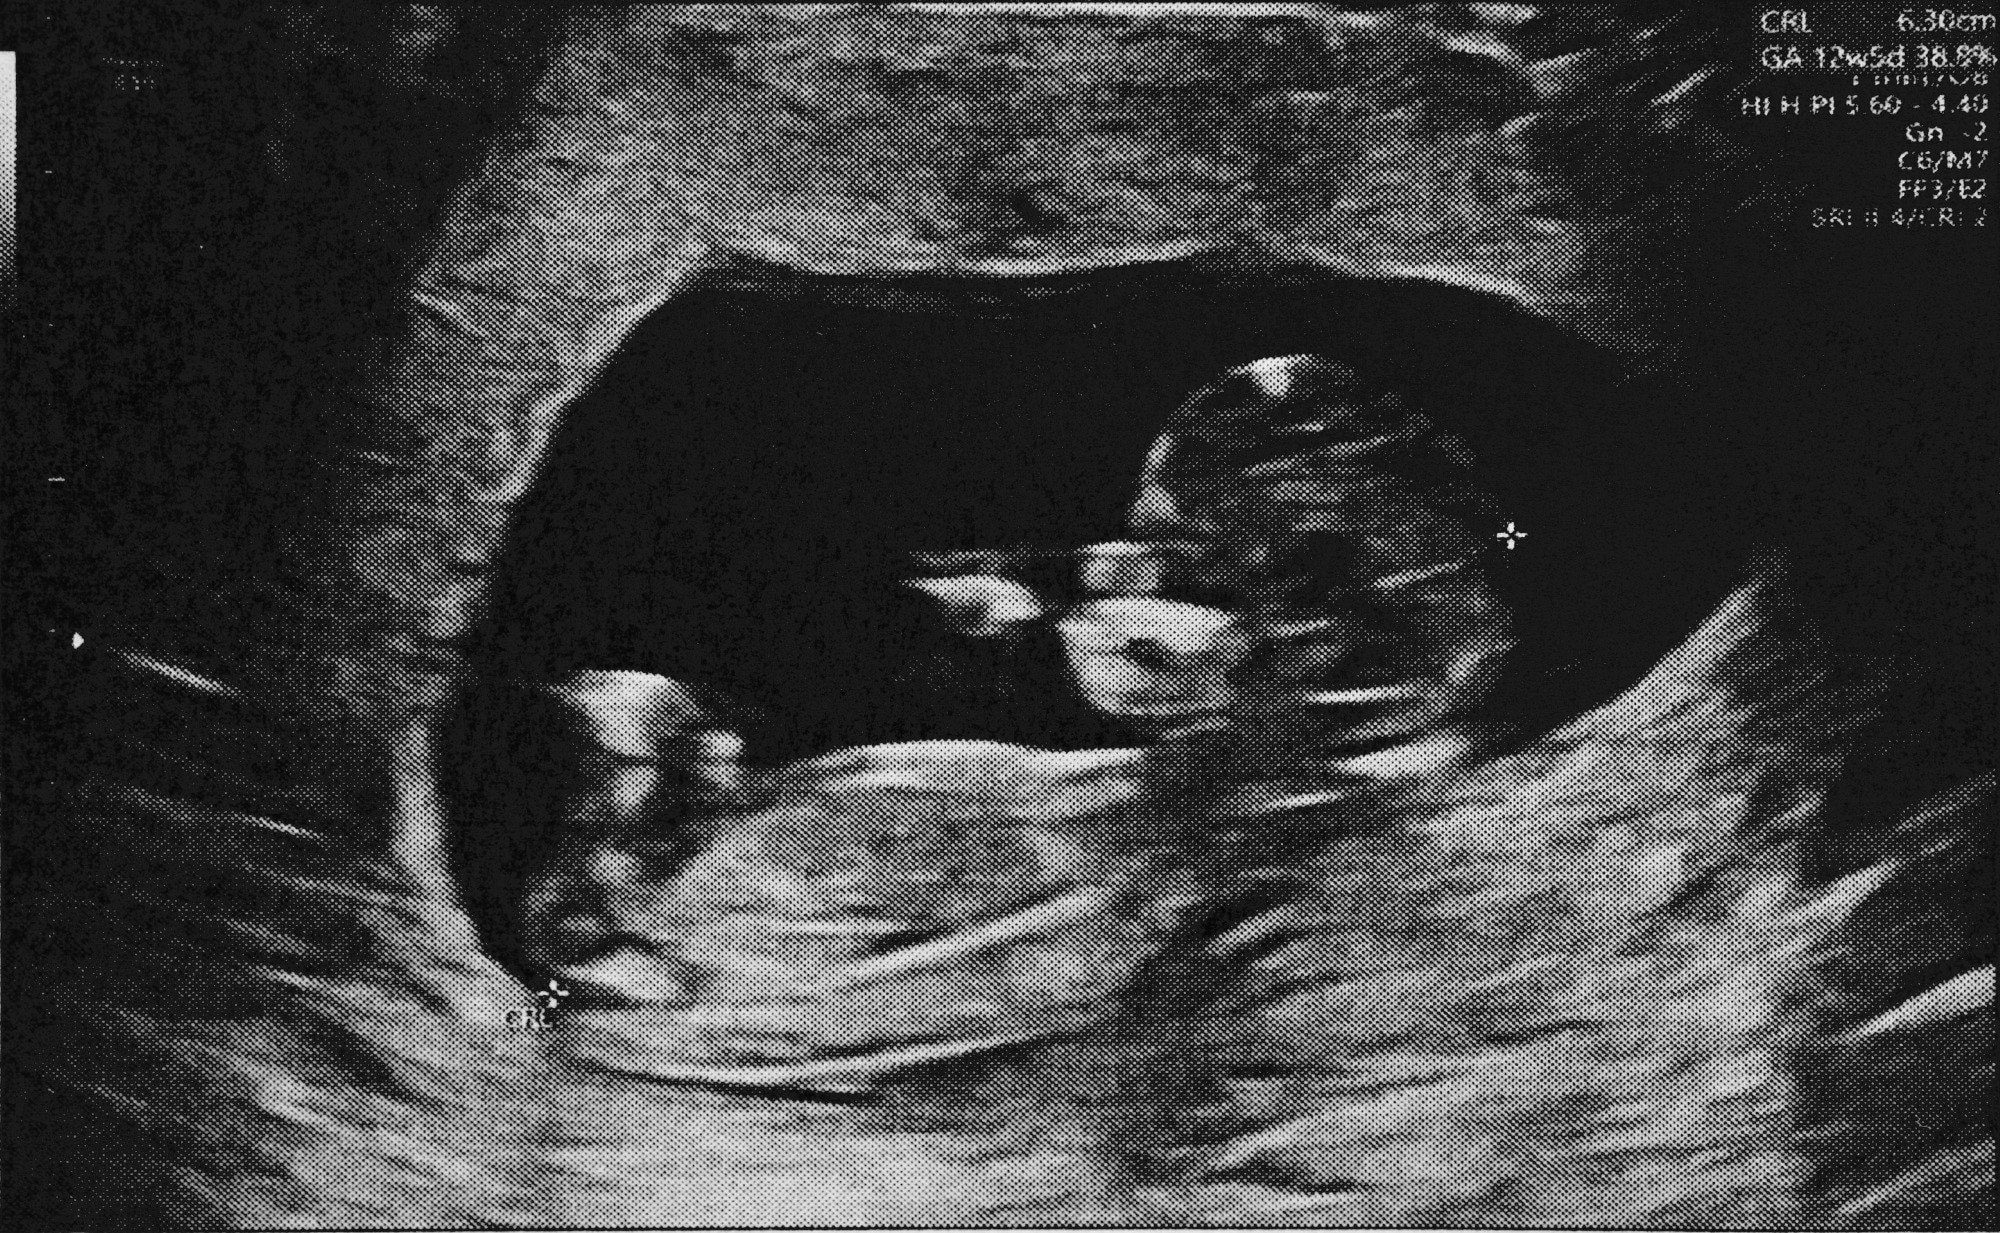

Study: Deep learning prediction of renal anomalies for prenatal ultrasound diagnosis. Image Credit: Tavarius / Shutterstock.com

Fetal ultrasound imaging is crucial for observing fetal anatomy and the presence of any malformations. Considering the high rate of congenital anomalies of the kidneys and urinary tract (CAKUT) at one in 500 live births, the incorporation of DL into prenatal screening could allow clinicians to diagnose these conditions earlier to improve patient outcomes.

About 970 ultrasound images were used to train the current study, which consisted of about 650 controls and 320 images of anomalous kidney anatomy. More specifically, about 260 images exhibited unilateral dilation of the urinary tract (UTD), whereas 64 were images of unilateral multicystic dysplastic kidney (MCDK).